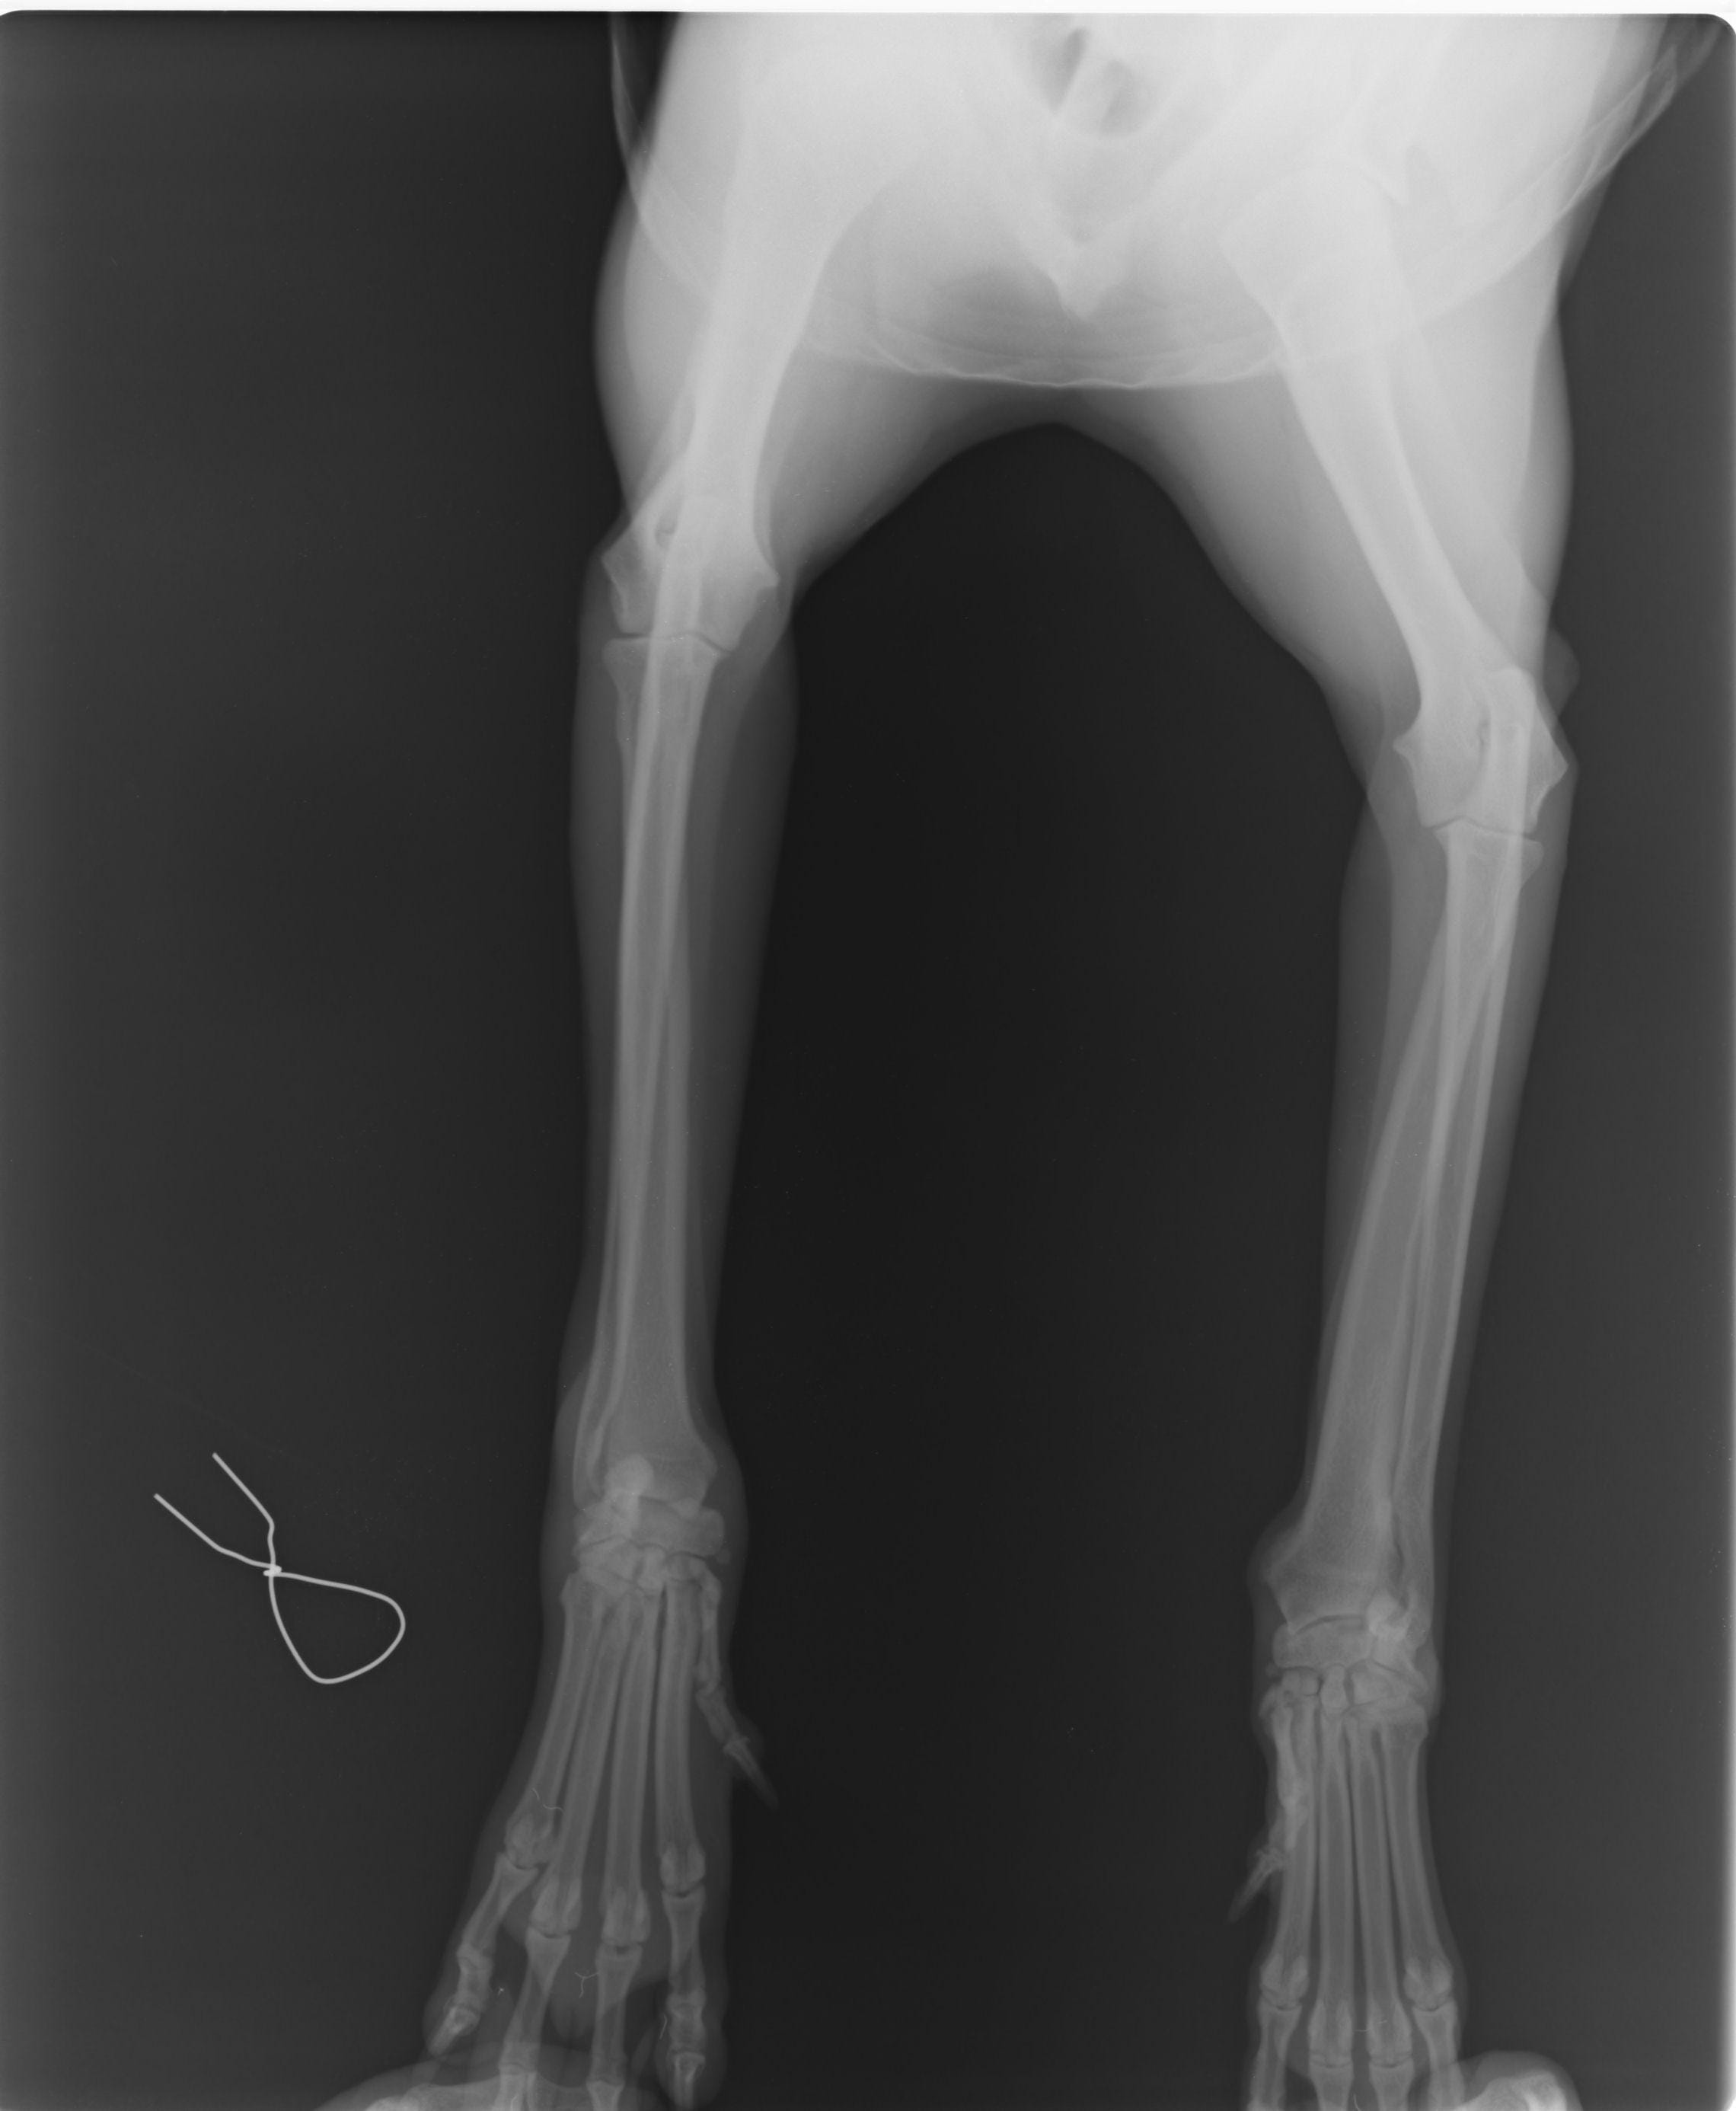

Hi. I live in lebanon and my belgian malinois has hurt her right wrist. I took her to the the 1st vet and he said that the swelling will go away and there was no fracture. I wasnt convinced so i took her to a 2nd vet who said that that there is fracture and he put a cast on her leg. Without a cast she shows signs of carpal hyperextension, but the vet said it isnt the case. From the xray images does it show a fracture, and if it does does it produce symptons of carpal hyperextension? Thanks a lot

It does look like there is fracture on the last phalang of what i assume is the right wrist (it's not indicated on the xray so can't know 100%), i cannot tell if it is causing symptoms of hyperextension from the xray but it was in my opinion the right decision to cast it for it to heal better.